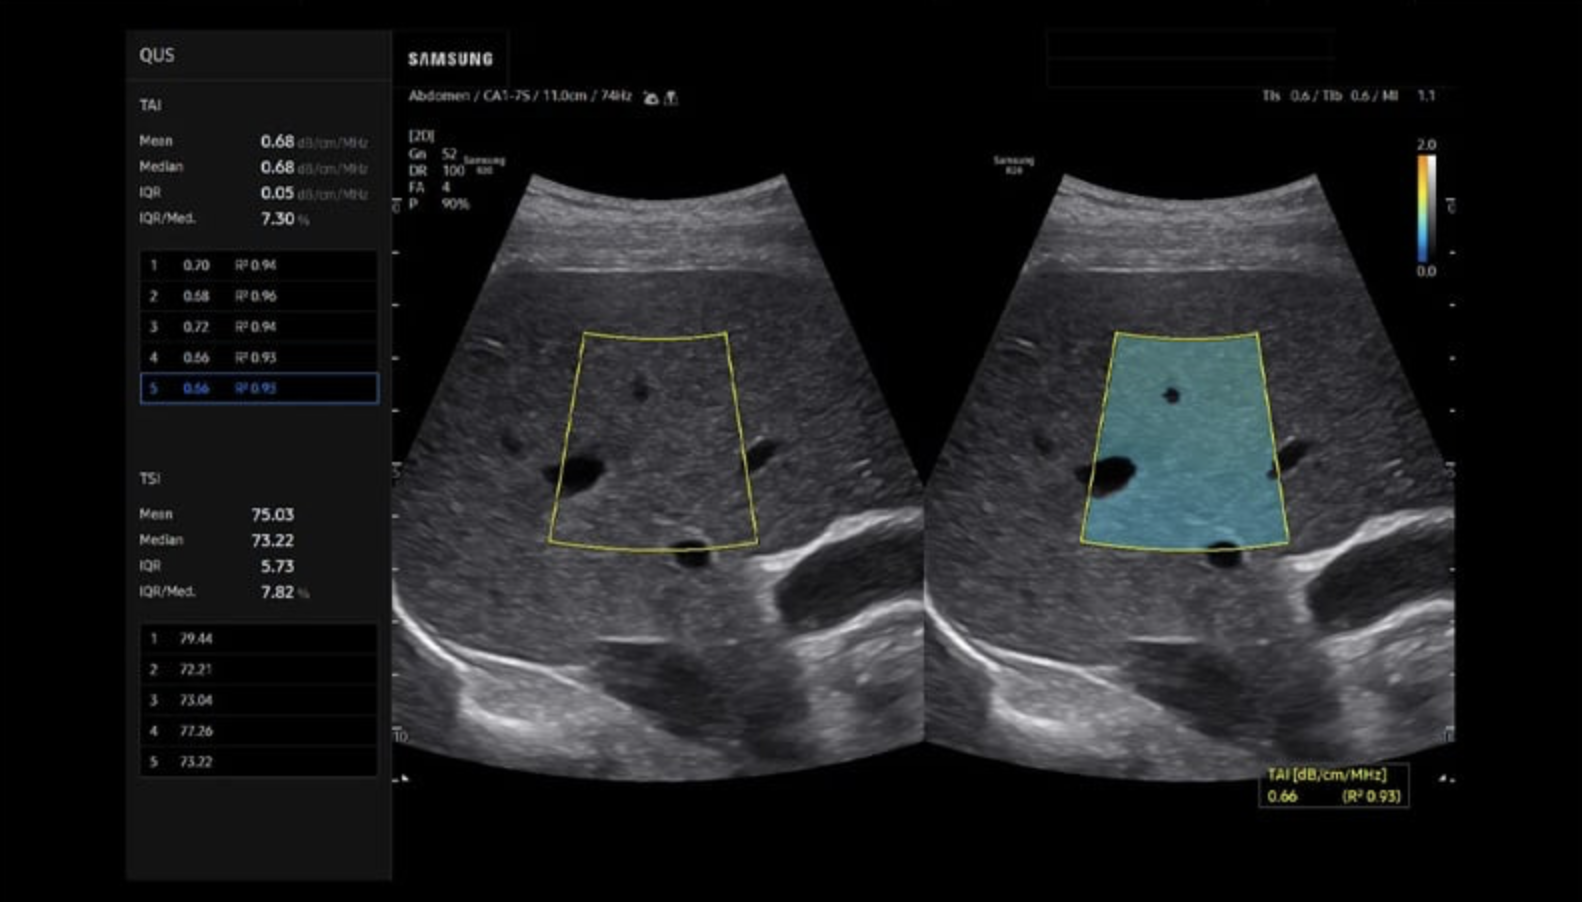

• The Science: We use high-frequency ultrasound to peer inside the tongue muscle.

• The Science: We scan the liver for Steatosis (fatty infiltration). The liver is the body’s engine. When it clogs with fat (due to sugar, alcohol, or stress), it releases inflammatory chemicals that inflame the airway and disrupt brain signals.